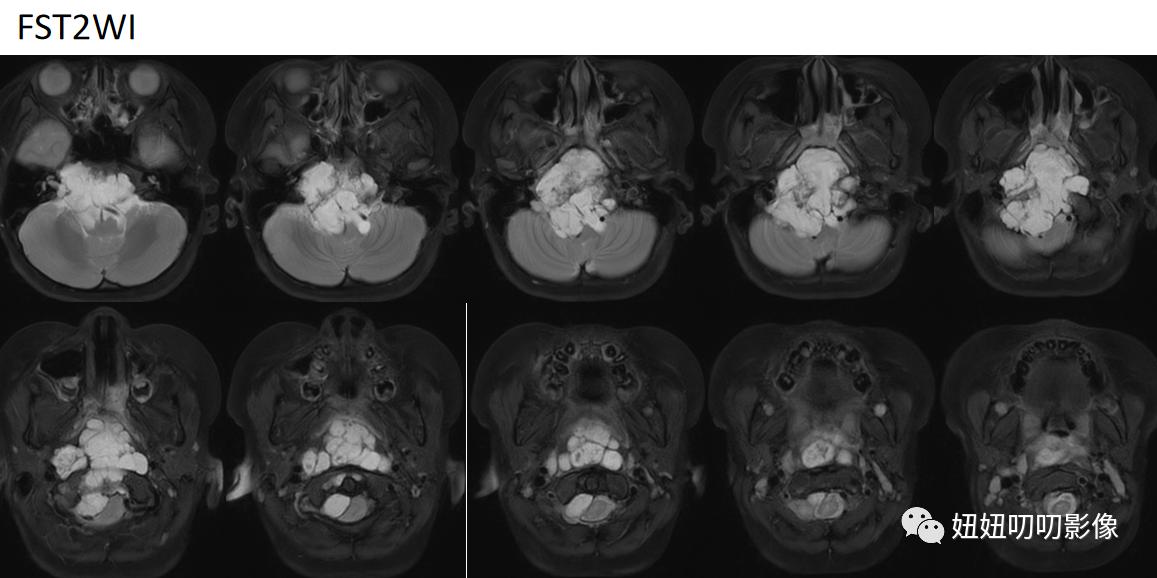

斜坡区见大小约5.6×5.7×6.1cm之不规则长短T1、长短T2信号肿块,其内见T2低信号分隔,DWI呈不均匀高信号,ADC图呈等低信号,增强呈明显不均匀强化,斜坡、枕骨骨质不同程度破坏,肿块向前凸向鼻咽口咽部,并推压斜坡-椎前软组织及双侧下鼻甲后部,局部增厚FS-T2WI呈稍高信号,双侧咽隐窝显示不清,向后压迫桥池及脑干延髓后方脑组织,第四脑室受压变扁,小脑扁桃体变尖下移,紧贴右侧听神经,部分包绕椎-基底动脉。

MRI:斜坡区异常信号灶,符合脊索瘤MRI表现,请结合临床及病理学检查。